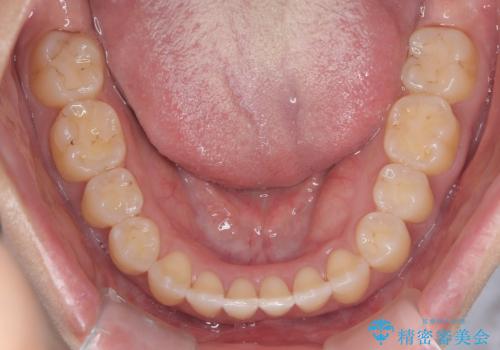

再矯正 前歯のガタツキをマウスピース矯正で治療したい

- 前に矯正治療をしたが、後戻りしてガタツキが出てきたので、治したいとのことで来院されました。

ワイヤー治療とマウスピース矯正、2通りの治療を提案させていただき、マウスピース矯正治療を希望されましたので、インビザラインによる治療を開始しました。

前歯のガタツキを改善する治療法として、マウスピース矯正が適していることが多いです。

マウスピース矯正は、金属製のブラケットやワイヤーを使用せずに、透明なマウスピースを装着して歯を移動させる方法です。そのため、目立たず、痛みも少ないです。